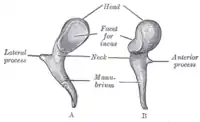

Martillo izquierdo: A. visto desde afuera. B. visto desde adentro. | ||

- Cabezaː forma parte superior del martillo. Está situada superiormente a la membrana timpánica, es decir, en el receso epitimpánico. De forma ovoide, la cabeza del martillo es regularmente lisa, salvo en su parte posterior, donde presenta una excavación articular elíptica con el eje mayor orientado oblicuamente en sentido inferior y medial. El extremo inferior de esta carilla articular ocupa la cara medial de la cabeza. Una cresta casi vertical la divide en dos vertientes, una posterior y otra medial. Por esta cara articular, el martillo se articula con el yunque.

- Cuelloː es la parte estrecha que sirve de soporte a la cabeza. Es corto y aplanado de lateral a medial; se relaciona lateralmente con la porción fláccida de la membrana del tímpano.

- Apófisis lateralː (apófisis corta), de forma cónica y 1 mm de largo, se origina inferiormente de la cara lateral del cuello. Se dirige lateralmente y da origen, en la cara externa de la membrana timpánica, a la pequeña eminencia cónica en que terminan los pliegues maleolares.

- Apófisis anteriorː (apófisis larga) nace en la cara anterior del cuello. Es alargada y muy delgada, se dirige posterior y anteriormente y tiene continuidad con el ligamento anterior del martillo.